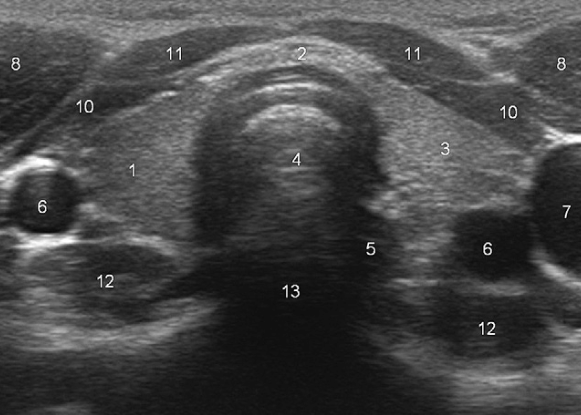

What does “5” represent?

Esophagus

What does “8” represent?

Sternocleidomastoid muscles

What do “10” and “11” represent?

Strap muscles (sternothyroid + sternohyoid)

What does “12” represent?

Longus colli muscles

This pseudo-micronodular appearance of the thyroid is characteristic of:

Hashimoto’s thyroiditis